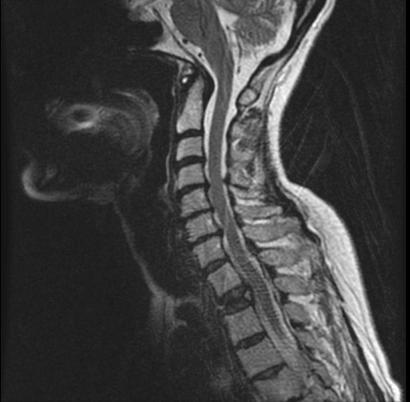

当然如果条件允许,也可以进行核磁检查,明确是否存在着颈椎间盘的突出以及曲度的改变。